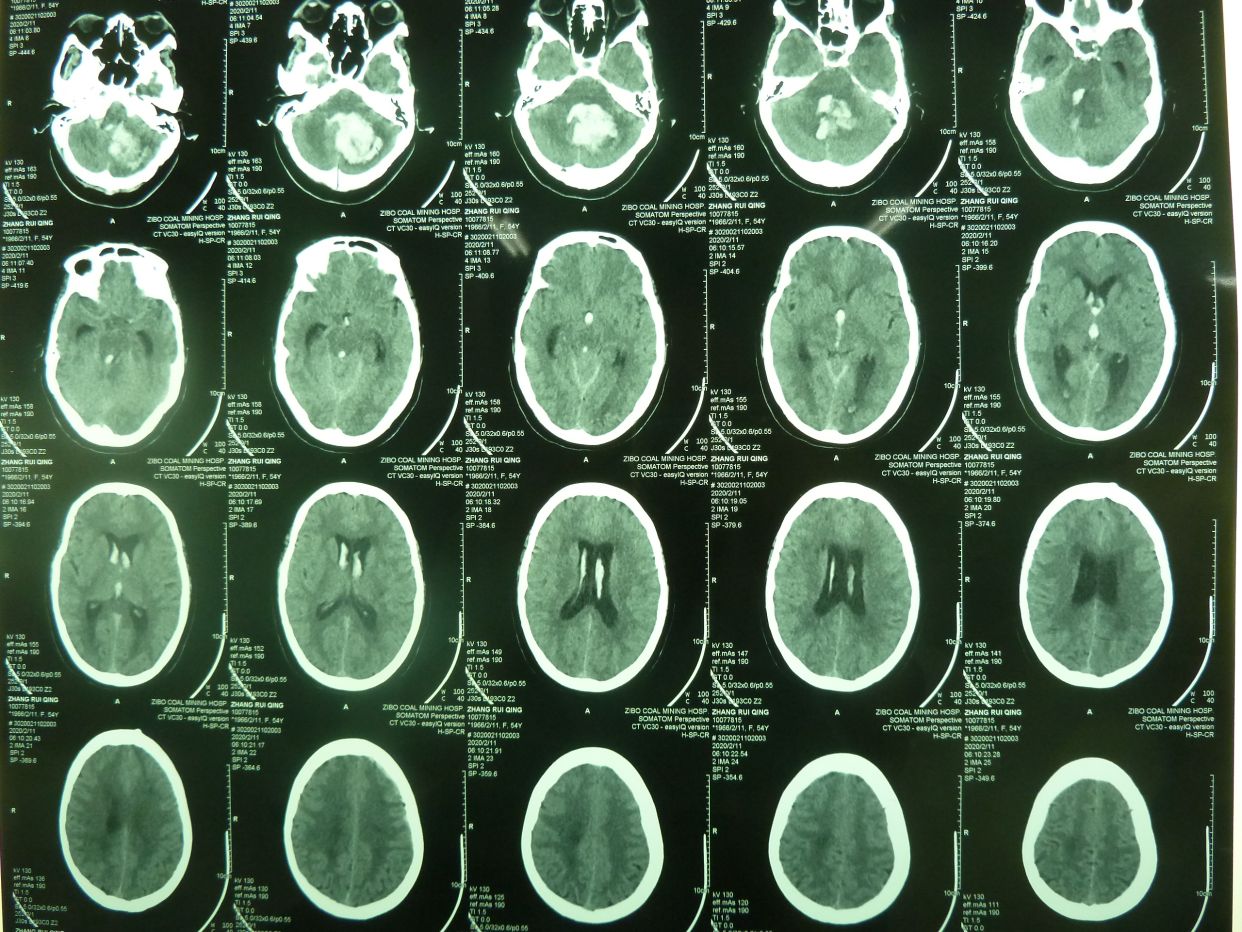

例2,患者女,54岁,突发头痛并意识不清3小时入院,有高血压、冠心病史多年,深昏迷,入院时出现呼吸停止,行气管插管,机械辅助呼吸。

CT示,小脑大量出血破入全脑室并梗阻性脑积水,与家属沟通并签字后急症行脑室外引流术,后颅凹开颅血肿清除术。

术后1天CT复查示,血肿清除满意,基底池可见,患者刺激睁眼。

患者术后1月,神志清,正确回答问题,四肢话动良好,出院康复。